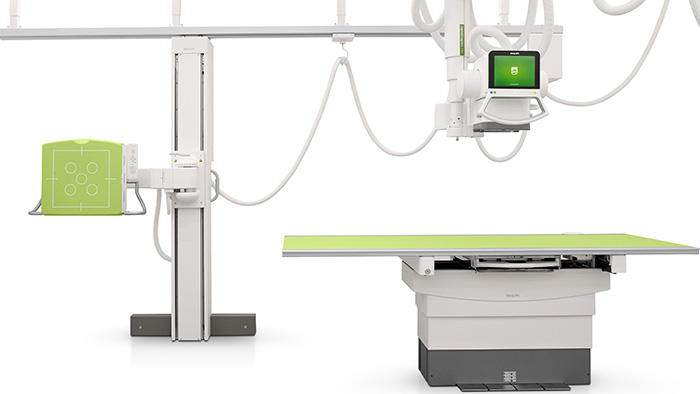

Radiography & Fluoroscopy Systems

Radiography & Fluoroscopy systems

Digital Radiography